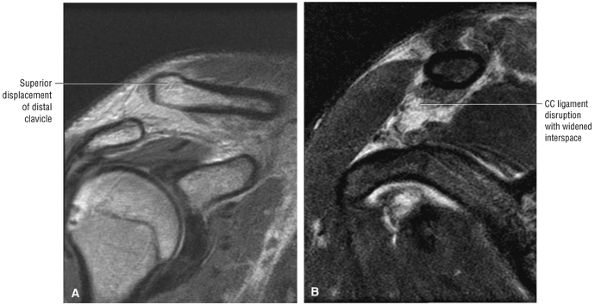

The clavicle connects the axial and appendicular skeletons of the upper extremity.44 It is S-shaped in configuration, with a convex anterior border medially and a concave

P.1195P.1196

anterior border laterally. It is flattened and narrowed laterally and has a thicker cylindrical configuration medially. The clavicle articulates with the sternoclavicular joint medially and with the AC joint laterally (Fig. 8.57). The surfaces of the sternoclavicular joint are covered by fibrocartilage, and a fibrocartilaginous articular disk divides the joint into separate recesses.45 -

The coracoclavicular ligaments are also displayed on anterior coronal oblique images. The anatomy of the AC articulation is best displayed at the level of the supraspinatus tendon. When present, AC joint fluid may represent an asymptomatic manifestation of osteoarthritis.41